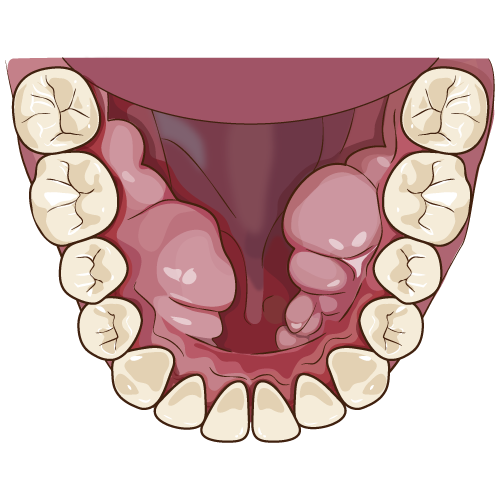

ソケットリフトとは、上顎洞底挙上術と呼ばれています。上顎骨の再生手術のひとつです。口の中から、上顎洞の底を持ち上げて、インプラントの埋入に必要なスペースを確保する処置になります。上顎洞の形には、個人差があり必ず必要な処置ではありませんが、感染により上顎骨の吸収が大きい場合は、人工骨や自家骨の補填では十分なスペースが確保できない場合に行います。

口腔内の当該部位の歯肉を切開します。その後、骨を上顎洞近くまで削っていきます。この際、削る量や深さは、事前にCTにて計算しておきます。その後、オステオトームと呼ばれる先端がノミのようになった器具で上顎洞まで進めていきます。オステオトームには、ストッパーがついていますので安全に処置することが可能です。その後、必要に応じて、骨補填材を使用して、上顎洞内の粘膜を挙上していきます。インプラントを同時に埋入する場合がほとんどです。粘膜の挙上する大きさによっては、適応にならないことがあります。一般的には、浸潤麻酔のみで処置しますが、静脈内鎮静法や笑気麻酔を併用することも可能です。